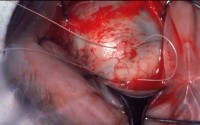

4. cryopexy

while vieweing with indirect opthamocope indirect sclera gently with tip of cryoprobe

->freeze break until sensory retina just turns white

4. Encircling procedure

5-0 ethibond 로 suture (cvd needle)

->suture한 부위에 silicone tube 506의 끝을 뾰족하게 scs로 자른 후 넣는다.

(미리 silicone tube 506은 GM bss 용액에 담아 놓는다)

->SB Set내에 있는 ㄱ자 fcp으로 insertion

->cut scs: wescott , retractor: 주걱모양

assist 의 손이 부족 하기 때문에 주걱모양 retractor 사용시 도움이 필요

교수님께서 suture할 때 black silk 당긴 채 suture